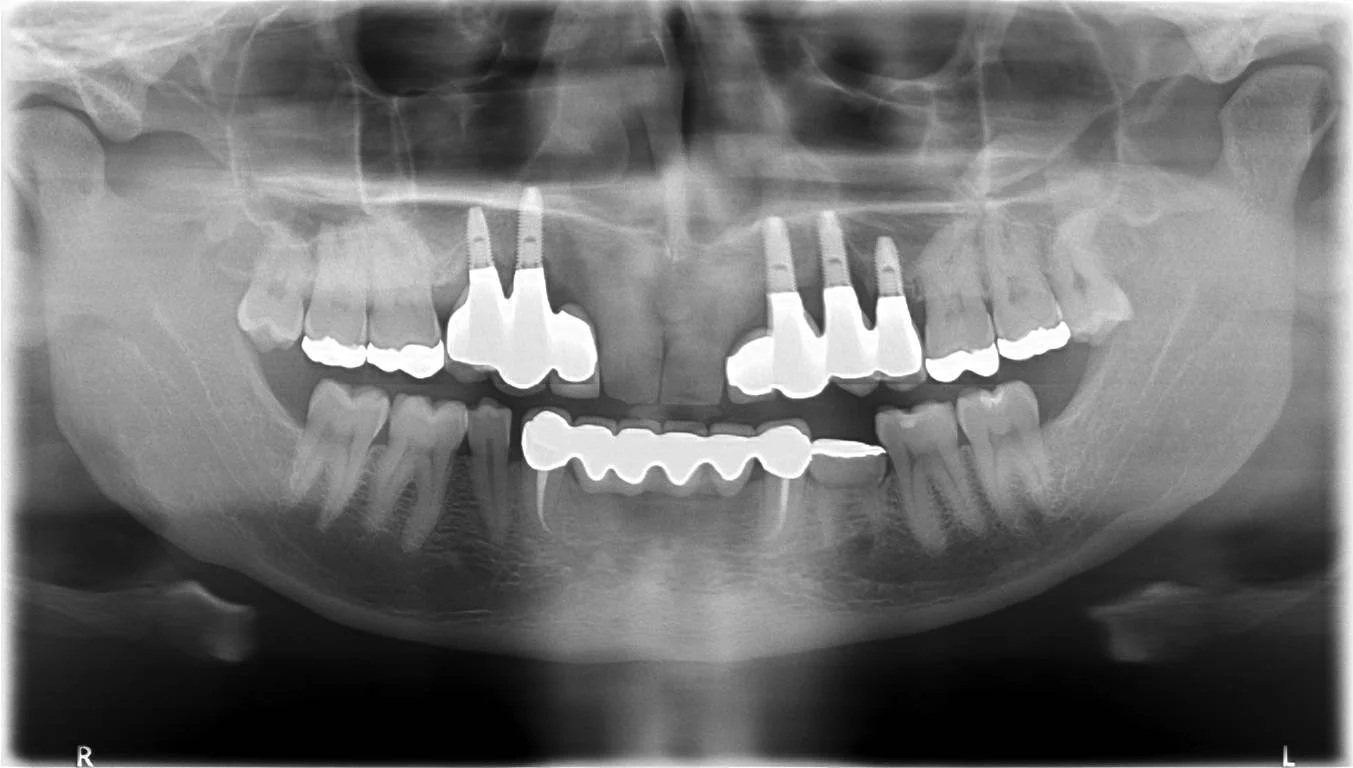

Throughout my 5 years at dental school I had bone grafts to move bone from my lower jaw to my upper jaw, placement of implants and bridges. Changes in my bite height and occlusion, eventually ditching my dentures by the age of 21.

You don’t have to be a dentist to see that my photo and x ray are different to most mouths.